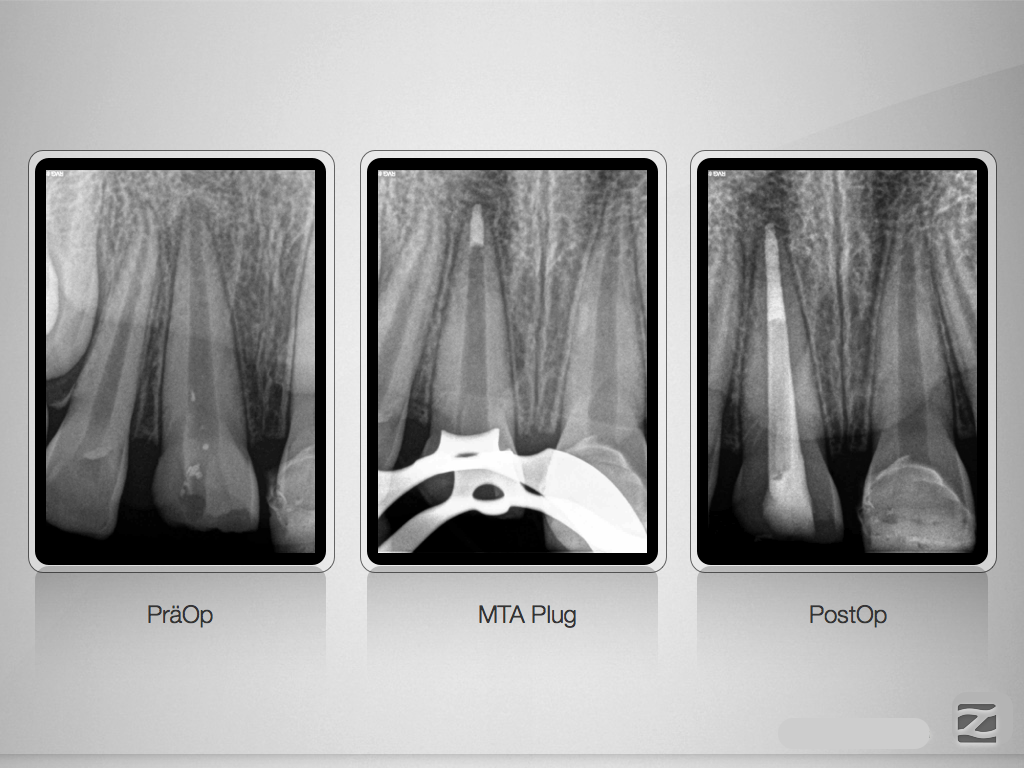

11D.003

Obturation statt Revitalisierung